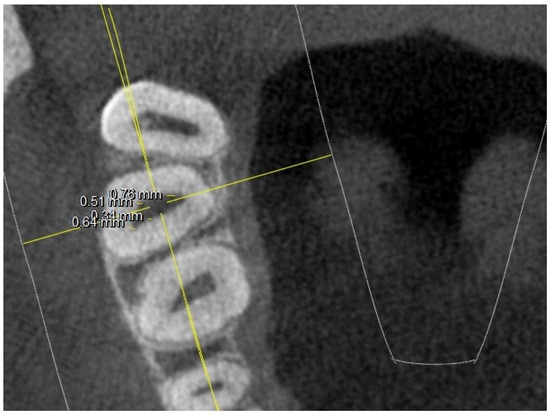

- diameter of root canal orifices;

- distance between intra- and inter-root canals;

| 5 mm from the CEJ: MB diameter | 0.74 | 0.26 | 0.85 | 0.21 | 0.74 | 0.24 | 0.8 | 0.22 | ||

| DB diameter | 0.79 | 0.14 (2 NO) | 0.65 | 0.11 (1 NO) | 0.75 | 0.12 (1 NO) | 0.68 | 0.12 (3 NO) | ||

| Palatal diameter | 1.19 | 0.07 | 1.1 | 0.06 | 1.35 | 0.06 | 1.19 | 0.06 | ||

| MB2 diameter | 0.42 | 0.6 (2 NO) | 0.47 | 0.5 (7 NO) | 0.47 | 0.7 (3 NO) | 0.42 | 0.4 (11 NO) | ||

| 5 mm from the CEJ: MB-DB distance | 4.35 | 0.82 | 2.88 | 0.62 | 4.13 | 0.78 | 2.97 | 0.64 | ||

| DB-P distance | 5.65 | 1.03 | 5.42 | 1.12 | 5.44 | 1.23 | 5.1 | 0.98 | ||

| P-MB2 distance | 5.94 | 1.45 | 4.94 | 1.44 | 5.61 | 1.65 | 3.28 | 1.12 | ||

| MB1-MB2 distance | 1.98 | 0.62 | 1.52 | 0.44 | 1.9 | 0.4 | 1.32 | 0.42 | ||

| MB-P distance | 7.56 | 1.7 | 6.55 | 1.55 | 7.14 | 1.52 | 5.68 | 1.49 | ||